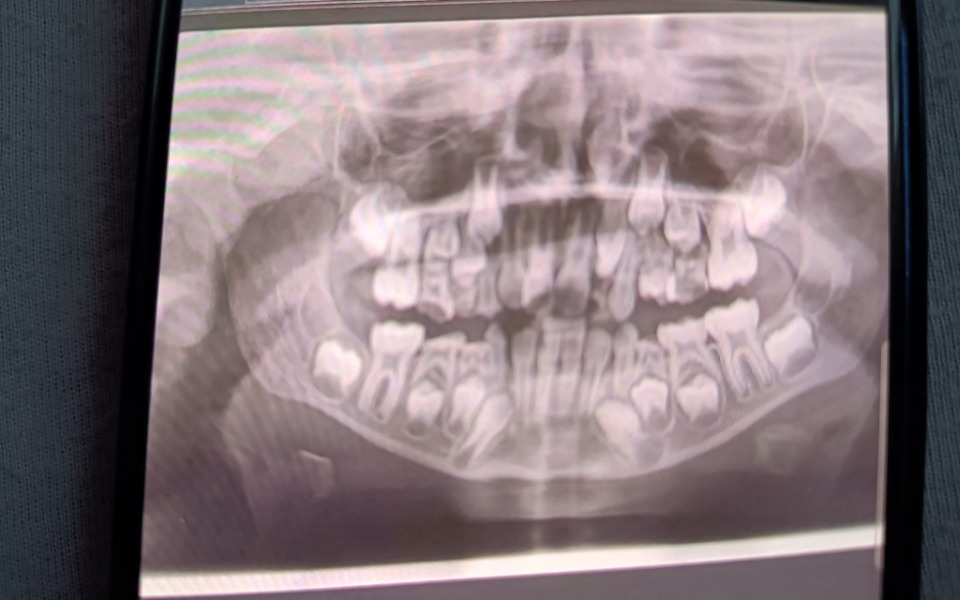

Jestem mamą 3 dziewczynek niestety najstarsza córka wymaga chodzenia do prywatnej kliniki stomatologicznej gdyz na NFZ nie kwalifikuje się każda wizyta to koszt 200 zł plus do tego założenie aparatu wyniki pobranie krwi to również są koszta. Chce by córka nie miała w przyszłości dalszych problemów a ma dopiero 9 lat proszę o mała cegiełkę gdyż dla mnie to bardzo ważne . I dziękuję za każdą pomoc